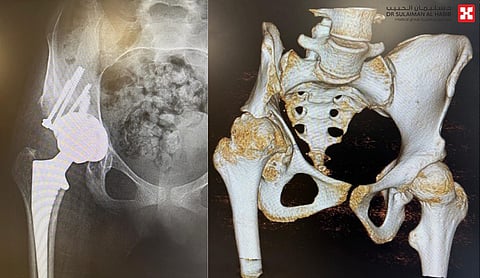

وأضاف د.عرفان أن الفريق الطبي أخضعها للفحص السريري الكامل، ومن ثم أُجريت لها بعض التحاليل وصور الأشعة في وضعيات مختلفة، والرنين المغناطيسي Mri، لتقييم وضع الأنسجة الضامة للمفصل والأربطة والهياكل الداخلية للمفصل، فأظهرت النتائج وجود خلع وتآكل في المفصل، تسبب في أن ينقص طول الطرف السفلي الأيمن 7 سم عن الأيسر.

وأضاف د. عرفان الحاصل على البورد والزمالة الكندية، أن الحالة أجريت لها عملية تم فيها استبدال مفصل الورك، وتركيب دعامة عظمية في الحوض لإعادة تأسيس المفصل، وتكللت جهود الفريق الطبي -ولله الحمد- بالنجاح التام؛ إذ استطاعت المراجعة خلال 24 ساعة من الإجراء الطبي، الوقوف والمشي بمساعدة أخصائيي العلاج الطبيعي، وفي وقت لاحق تخلصت من معظم الأعراض التي عانت منها، وتراجعت حدة ما تبقى منها، وستختفي إن شاء الله، بعد استكمال برنامج العلاج الطبيعي.